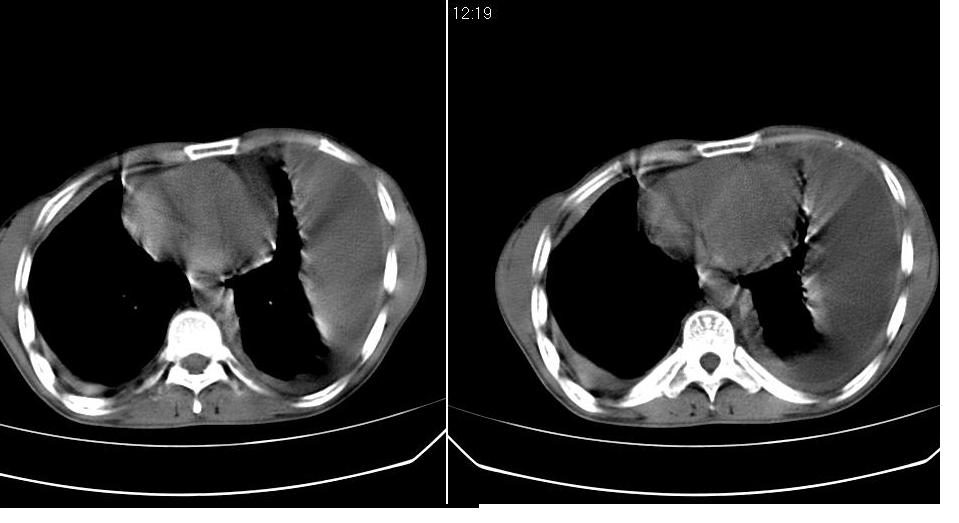

以下是引用苯小孩在2007-6-27 15:09:00的发言:[br]考虑:1、右肺继发性肺结核.2、双侧包裹性积液<胸腔及叶间>3、双侧局部胸膜增厚.[br]建议胸水化验检查.

以下是引用yanghaochen88在2007-6-27 15:08:00的发言:[br]双肺上野散在粟粒状影、包裹性积液、胸膜增厚粘连、叶间积液---tb,至于分型还得结合病史体征细究妥当些。

以下是引用zjzjr在2007-6-27 16:49:00的发言:[br]肺结核、结核性胸膜炎。